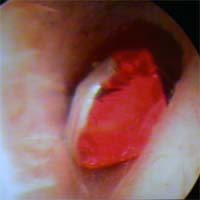

小学2年 左耳に紙を入れられ 聞こえなくなった 紙の異物除去後 聞こえるようになった 長さ 7mm 2019年9月19日  |